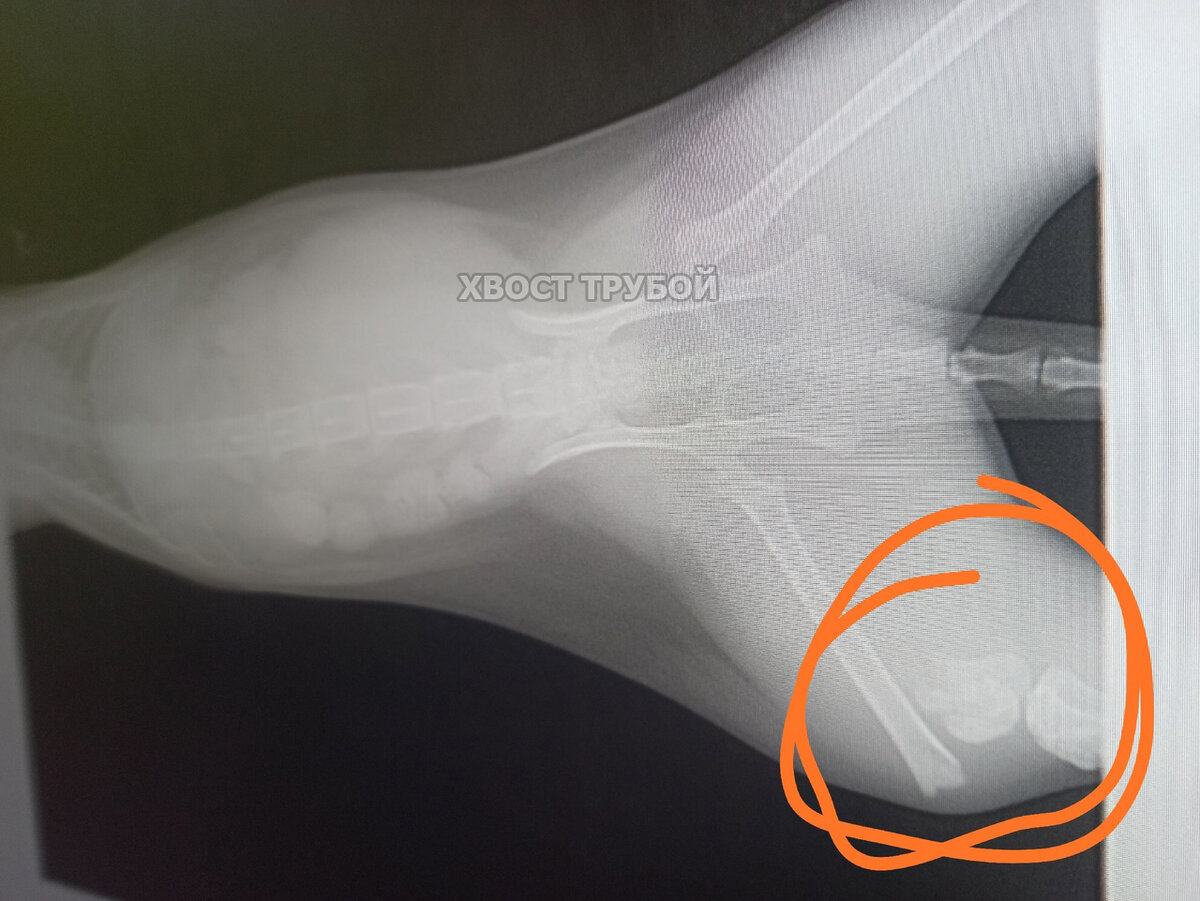

Она улетела в окно, когда хозяева что-то бурно праздновали. В ветклинику малышку привезли друзья хозяев, оказалось, что у бедняжки сло маны аж 3 лапки! Две передние и одна задняя. Кошечка приземлилась на лапы, это спасло ей жизнь, но лапки сильно пострадали. Оставив несчастную бедолагу в стационаре ветклиники, друзья хозяев уехали. А дальше началось нечто странное: сначала котейкой интересовались, потом неохотно брали трубку, потом и вовсе перестали отвечать на звонки.

Она улетела в окно, когда хозяева что-то бурно праздновали. В ветклинику малышку привезли друзья хозяев, оказалось, что у бедняжки сло маны аж 3 лапки! Две передние и одна задняя. Кошечка приземлилась на лапы, это спасло ей жизнь, но лапки сильно пострадали.

Наверное стоит пояснить, а то в комментариях уже открылись врата ада. Ляля не просто лежала в стационаре, как некоторым читателям показалось. За ней оказывался должный уход, ей делались капельницы, ей подмывали попу, потому что она не могла нормально сходить в туалет и не испачкаться, ей меняли пелёночки, ее даже первое время кормили из шприца, потому что она сама не ела. Сами операции в данном случае ее боль не облегчили бы. Как видно на первых фото, кошка находится в шоковом состоянии, в первые дни ее в любом случае бы не оперировали, а стабилизировали состояние. Чем, собственно, врачи и занимались. Две передние лапки начали срастаться самостоятельно. На задней лапке операция проведена сразу же, как только был получен письменный отказ хозяев от кошки. Мы не можем расписывать красочно все проводимые манипуляции и диагнозы, на Дзене есть определенные правила работы с каналами.

От Ляли, наконец-то, написали отказную, оплатили счета за стационар, и с момента отказа малышка находится под нашей опекой и кураторством. Ей провели операцию на одной задней лапке, передние уже нет смысла оперировать, косточки начали срастаться сами.